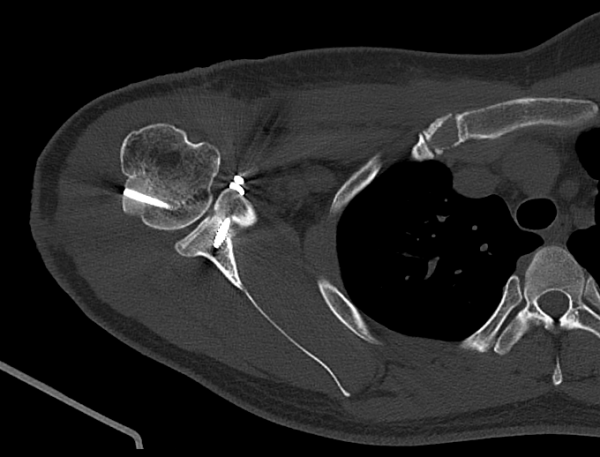

adafb-69420097ba372-6751fe1dd3f7e953ff967140b525a7d2773b25ab.png

adafb-694200ac62c11-721ff32081ab30f0209d46b26dcb9db23d614978.png

수술 후 첫 CT 결과에서 이식된 상완골두는 정렬 상태가 매우 우수하고, 결손 부위를 정확하게 메우고 있었습니다.

부기·염증수치·통증 모두 양호했고, 신경학적 문제 없이 손·손가락 운동도 잘 되었습니다.

환자는 8일 후 안정적으로 퇴원했고, 현재 외래 추적에서도 회복 경과가 좋습니다.